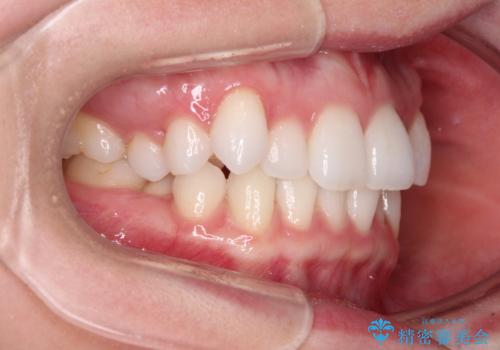

- 上下前歯のデコボコ、特に右上の八重歯を気にして来院された患者様です。

妊娠、出産の予定があり、毎月の通院が困難となる可能性があったため、インビザラインによる矯正治療を行うこととしました。

事前に親知らずを抜歯しておき、出産時期に困ることのないように準備をした上で治療を開始しました。

治療後半では悪阻によりマウスピースの装着時間が不十分となることもありましたが、それよりも前にしっかりと装着時間を守って治療を進めることができたため、特に気になるところなく治療を終えることができました。